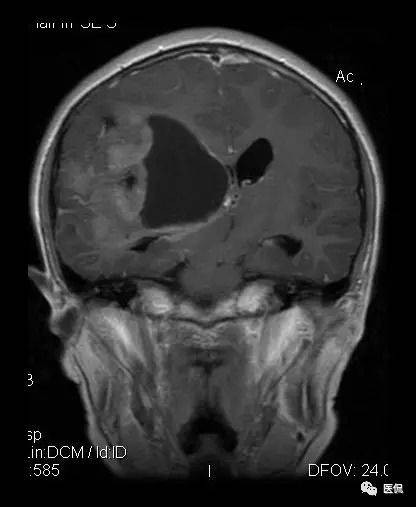

ZNF638与胶质母细胞瘤的秘密

说到胶质母细胞瘤(GBM),这是目前最致命的一种脑肿瘤之一。最近有研究发现,ZNF638在胶质母细胞瘤组织中的表达水平显著高于正常脑组织,这提示它可能在肿瘤发生发展中扮演重要角色。